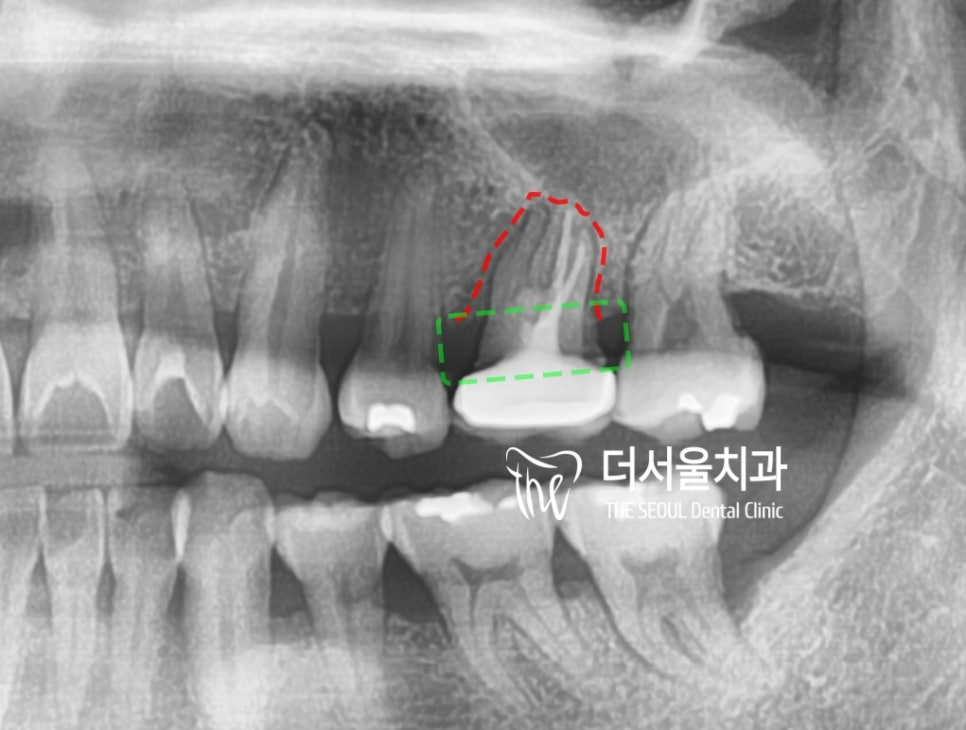

안녕하세요. 박현준 원장입니다. 제가 3년전에 적었던 글을 하나 보여드릴게요. (최근에 치료가 끝났거든요!) 이전 글의 내용을 정리하면 순서로 설명을 드렸었습니다.